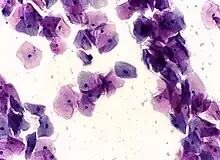

Squamous metaplasia of the cervix, with typical features. Pap stain.

Pap tests commonly examine epithelial abnormalities, such as metaplasia, dysplasia, or borderline changes, all of which may be indicative of CIN. Nuclei will stain dark blue, squamous cells will stain green and keratinised cells will stain pink/ orange. Koilocytes may be observed where there is some dyskaryosis (of epithelium). The nucleus in koilocytes is typically irregular, indicating possible cause for concern; requiring further confirmatory screens and tests.